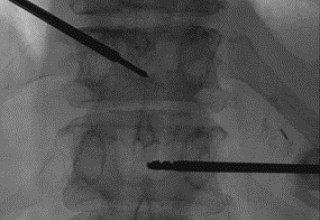

Vertebral body tumor access

The microwave energy ablation of vertebral-body tumors provides the doctors with additional capability for controlling and relieving pain when used in conjunction with cementoplasty (bone cement filling.)  Microwave energy application is controlled with direct temperature feedback from the ablation antenna during the procedure to ensure safety and efficacy.

AveCure® microwave ablation system is successfully used to treat and relieve pain from metastatic vertebral-body tumors and bone cement is used to fill the remaining cavity to restore the mechanical structure. The procedure is minimally invasive. A bone cannula is inserted through a skin incision to access the tumor and the patient is left with a small hole in the skin, which quickly heals with almost no scar after the procedure. The AveCure® ​system utilizes a smart antenna in either probe or catheter format and a microwave energy controller to select the correct size, temperature and timer settings appropriate for safe, effective and predictable treatment.